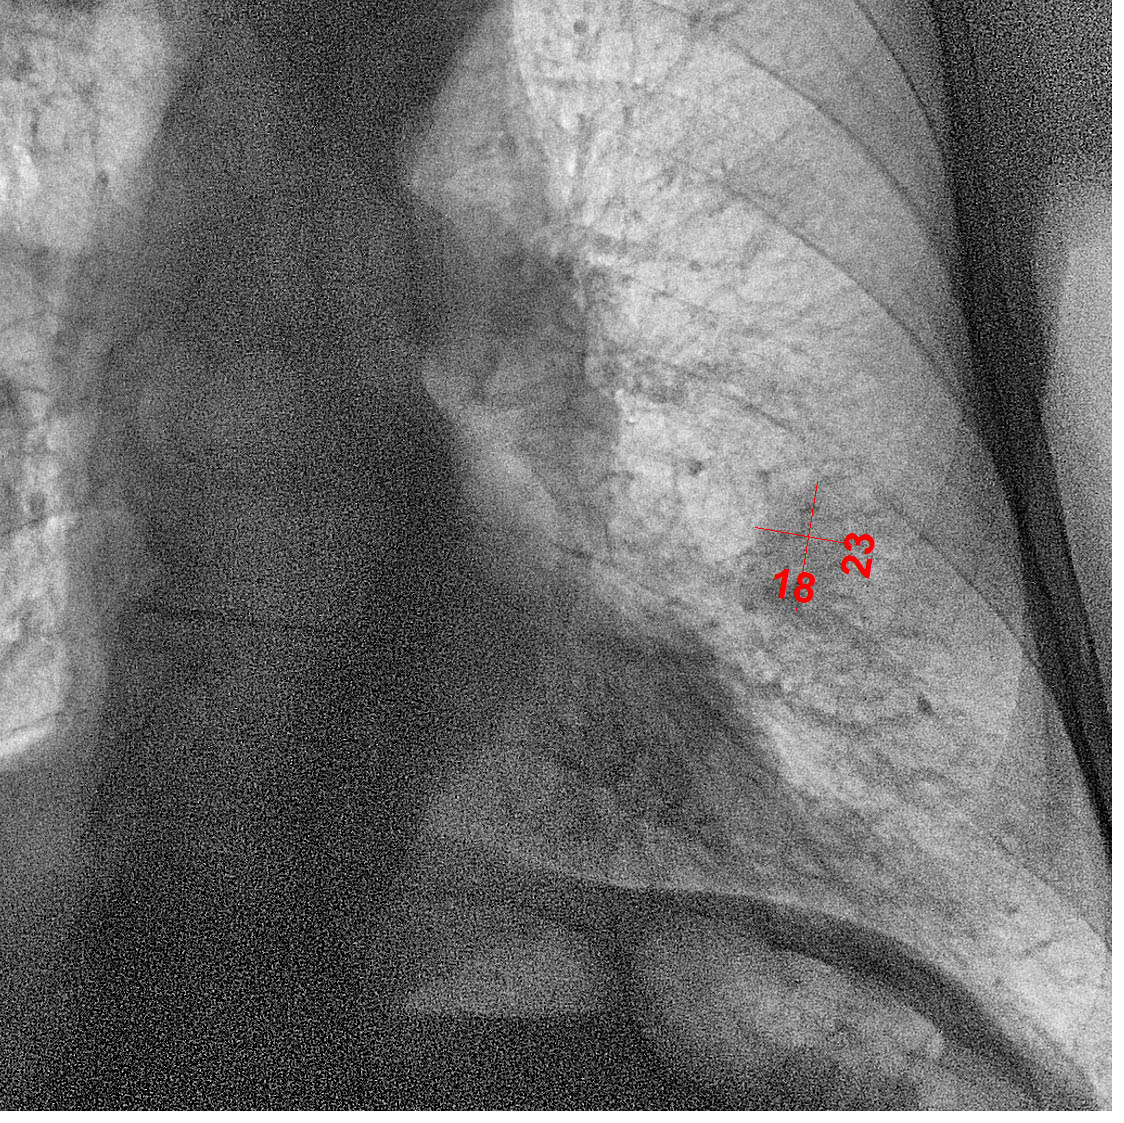

Добавляю наверх последние снимки, декабрьские.

Тут уже всё ясно. Синдром Панкоста во полном объеме. Картина патогномонична. Случай почти студенческий.

Несколько странно выглядят метастазы. А ребра I  и II  целёхоньки. Вот задние отд. III  и IV  разрушены.